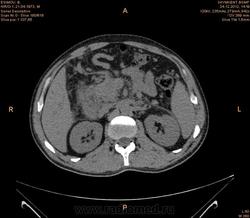

Предварительно образование головки ПЖ, и в печени. Что с ферментами?

на операций рак головки подж.железы с метастазир. печень.

инфильтрация тут нисходящей 12 перст кишки , расширенного холедох,расширенный вирсунгов проток ,нижная граница очень близко прилежит к нижней полой вене с правой почечной веной ,но четко визуализирутся передний листок фасции Героты(нельзя исключить ее инфильтрацию), инфильтрация конгломератом увеличенных лимфатических узлов ворот печени портальной вены с варикозным расширением вен, на вышележащий срезах четко определяются верхняя брыжеечная вена и артерия ,не хватает срезов для полной визуализации(помогли бы мпр),инфильтрирована восходящая ободочная кишка,конгломерат лимфат узлов за головкой поджелудочной железы в виде гиподенсивного участка вытянутой формы , ,мтс в печень,парааортальные